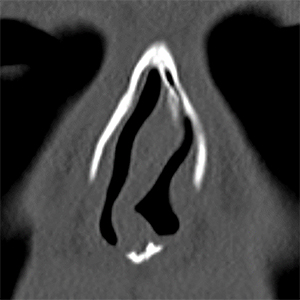

左:鼻中隔軟骨の骨折 右:篩骨正中板の湾曲

上:鼻中隔軟骨の骨折 下:篩骨正中板の湾曲

機能面では鼻づまりの症状があり、CTで鼻中隔の曲がりを認め、一部外傷によると思われる中隔軟骨の骨折もありました。